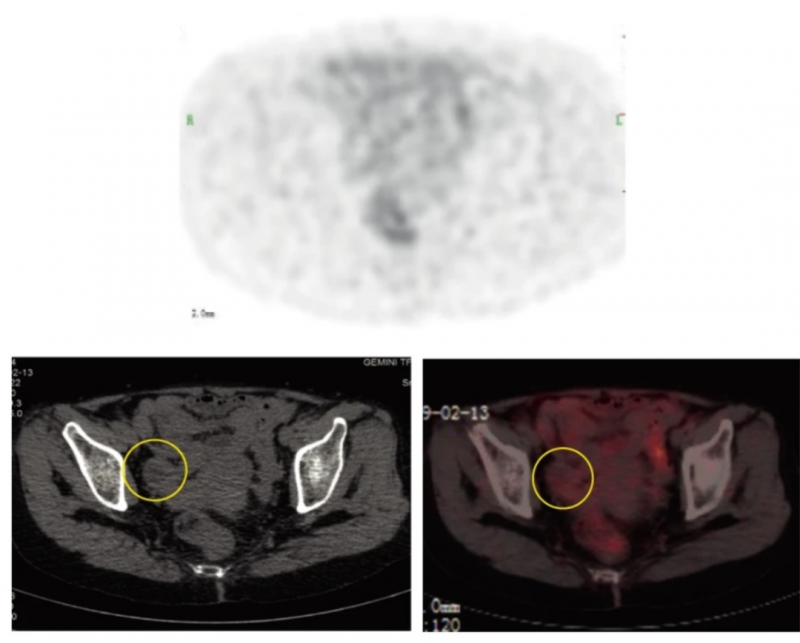

2、影像学检查:初次接种疫苗后第231天,PET示右侧卵巢病灶近乎完全消退(详见图1)。联合治疗第389天,CT示卵巢种植转移完全消失(详见图2)。截至2021年10月,CT显示完全消退持续25个月。

图1 治疗第231天,右侧卵巢PET/CT图像

▲图源“npj”,版权归原作者所有,如无意中侵犯了知识产权,请联系我们删除